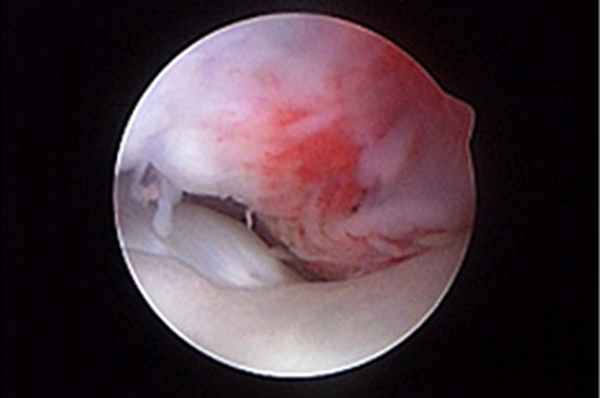

Травма сухожилия двуглавой мышцы

Сухожилие двуглавой мышцы берет начало от надсуставного бугорка и суставной губы плечевого сустава, на краниальной части суставной впадины. Сухожилие проходит через краниомедиальную часть головки плечевой кости по межбугорковой борозде и спускается ниже вдоль плечевой кости, где располагается мышечно-сухожильное соединение. Начало сухожилия находится в пределах сустава, но вне синовиальной оболочки. При этом сухожилие не движется в борозде, а наоборот, плечевая кость движется относительно сухожилия. Синовиальная сумка начинается от плечевого сустава и на большем своем протяжении лежит в межбугорковой борозде. К нарушениям сухожилия двуглавой мышцы относятся частичный или полный разрыв, отрыв сухожилия двуглавой мышцы от надсуставного бугорка, тендинит, разрывы в средней части, разделение сухожилия надвое, вывих сухожилия и тендосиновит.

Тендосиновит двуглавой мышцы – воспаление сухожилия двуглавой мышцы в месте его прикрепления, сухожильного влагалища и суставной сумки в пределах межбугорковой борозды плечевой кости. Воспаление может быть вызвано травмой, суставной мышью в сухожильном влагалище двуглавой мышцы или поражением внутренних структур сустава, например нестабильностью плечелопаточного сустава. Причина первичного повреждения неизвестна, предполагаемые причины включают перегрузку и хроническую многократную травму. Хроническая многократная травма приводит к биомеханическому напряжению и воспалительной реакции. Макроскопические патологические изменения включают гиперемию суставной сумки, приводящую к образованию выпота в суставе, хронический синовит, приводящий к гиперплазии синовиальной оболочки сумки, размягчение хряща межбугорковой борозды с образованием остеофитов по краям и метастатическое обызвествление сухожилия двуглавой мышцы. Возможно образование спаек между сухожилием и сухожильным влагалищем. Гипоксия сухожилия из-за нарушения кровоснабжения способствует хондроидной метаплазии и обызвествлению сухожилия двуглавой мышцы. Нормальное синовиальное пространство и гладкая поверхность скольжения межбугоркового желоба обычно замещается пролиферативной синовиальной оболочкой и в большинстве случаев фиброзными спайками. Иногда в суставе образуется обызвествленная или хрящевая ткань. Болезнь часто поражает крупных собак среднего и пожилого возраста. Хроническая хромота обычно ослабевает в покое, но усиливается при физических нагрузках. Боль, возникающая при скольжении сухожилия вдоль кости, ограничивает амплитуду движения в плечевом суставе во время фазы вынесения конечности. Диагноз ставится на основании болезненности при пальпации кожи над сухожилием в межбугорковом желобе при одновременном сгибании плеча и разгибании локтя, а также по рентгеновским снимкам, на которых можно увидеть обызвествление и остеофиты в межбугорковой борозде, а также ее контуры.

УЗИ считается полезным неинвазивным инструментом оценки сухожилия двуглавой мышцы. Артроскопия – самый рациональный метод лечения таких состояний, так как позволяет визуализировать сухожилие двуглавой мышцы в месте его прикрепления и иссечь сухожилие в пределах борозды артроскопическим способом (рис. 6-8). Кроме того, она позволяет оценить воспаление сухожилия двуглавой мышцы, развившееся вторично на фоне другой внутренней патологии сустава. Для лечения тендосиновита двуглавой мышцы можно применять артроскопическую тенотомию с помощью лезвия скальпеля или прибора для радиочастотной абляции. Это менее инвазивная техника, чем тендодез, при сходных результатах.

![]() | ![]() | ![]() |

| Рис. 6. Тендосиновит в месте прикрепления сухожилия двуглавой мышцы с разрывом волокон и гиперемией сухожилия. Рис. 7. Тенотомия сухожилия двуглавой мышцы с помощью радиочастотного зонда. Рис. 8. Снимок после тенотомии, сухожилие двуглавой мышцы скользит дистально в межбугорковой борозде. | ||